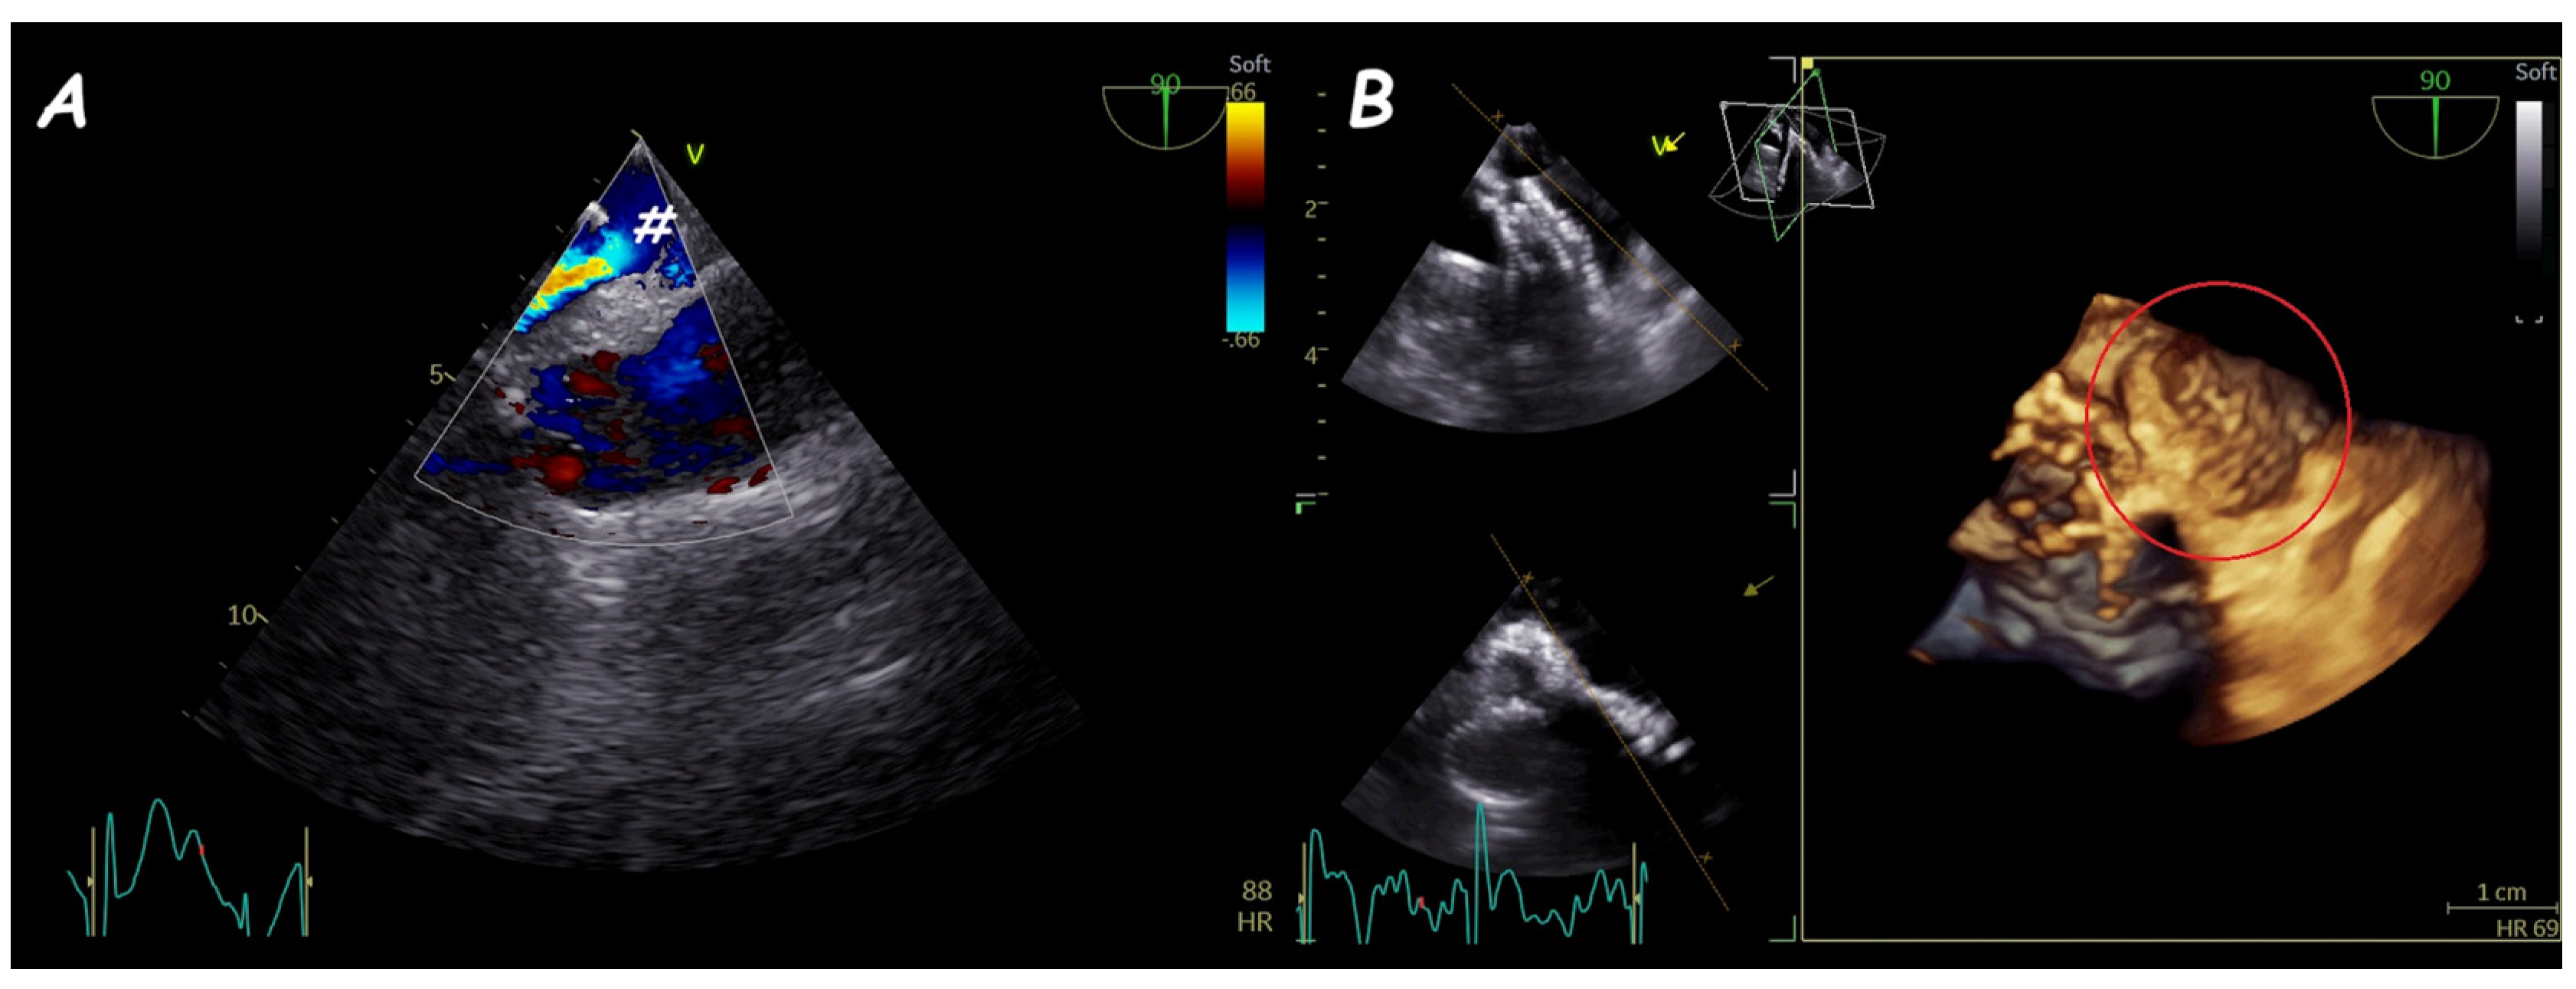

6. Ruptured Sinus of Valsalva Closure